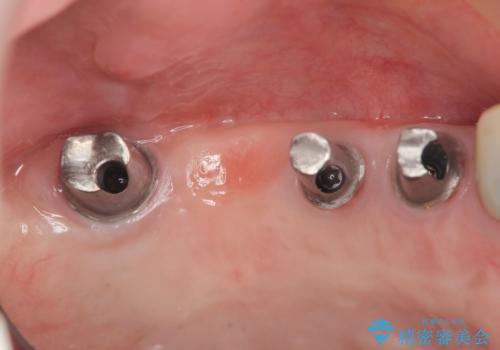

残すことのできない歯を抜去したのち、骨を造成し安定した環境下で長期的な予後を期待できるインプラント治療を計画します。

- 275万円(インプラント×5・チタンカスタムアバットメント×5・ジルコニアクラウン×7・仮歯×7)費用は治療当時の料金となります